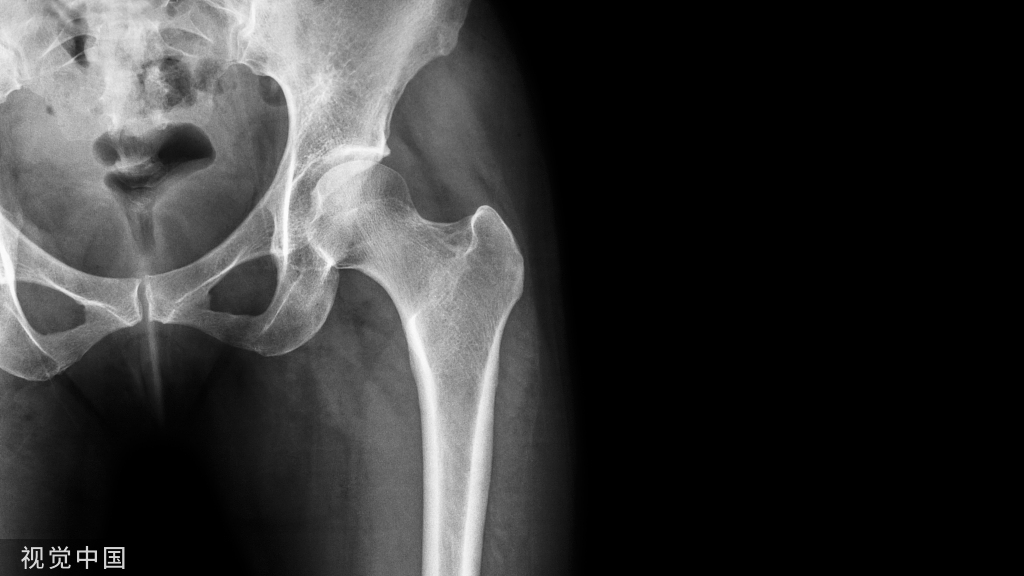

内固定术是用金属螺钉、接骨板、髓内针、钢丝、钛缆或骨板等物直接在骨内或骨外将骨折、关节或脊柱连接固定起来的手术。

内固定物的作用是为了维持稳定,如骨折对位对线后,使用内固定物维持对位对线并固定牢固。比如关节融合手术,为了维持准备融合关节的稳定以便关节融合,需要相应固定材料进行固定。再如脊柱退变手术,为了维持脊柱的稳定,避免出现或者为了纠正脊柱不稳,也需要内固定来维系。因此,在骨科很多手术中,进行内固定术是很常见的操作。

内固定物,是否要拆取?

内固定术,一旦骨折愈合、脊柱融合、关节融合等,内固定物就完成了使命,也就是说内固定物“没用”了,再加上内固定物材料大多系金属材质,对人体来说总归是异物。因此,大多数人都认为这时内固定物就应该取出来了。然而,事情并没有这么简单。

事实上,内固定物是否取,需要因不同情况而定。